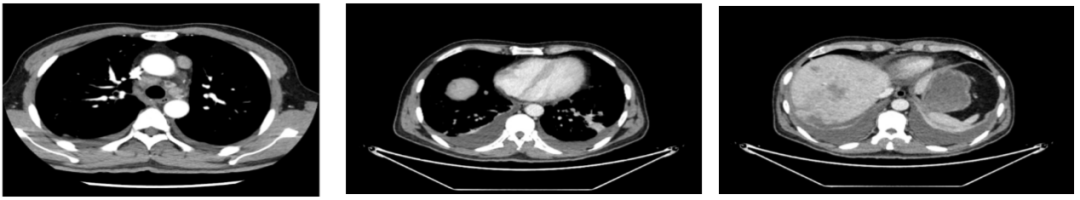

2020年4月复查:持续PR

增强CT示:肝硬化

肝异常强化灶

考虑酒精性肝硬化可能性大,未基线使用替吉奥维持治疗。

胃癌并肝转移化疗后,肝内转移灶大致同期;

慢性肝病,脾大、门脉高压(食管下段-胃底静脉曲张);

右肺中叶外侧段、左肺上叶下舌段及右肺下叶后基底段慢性炎症;

右肺上叶前段实性微小结节,炎性结节?建议定期复查;

纵隔淋巴结转移瘤,复查大致同前。